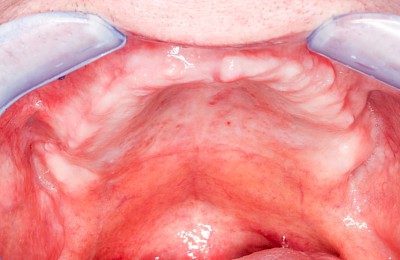

Knochenschwund (Atrophie)

Gehen die Zähne verloren, baut häufig auch der Kieferknochen ab (Knochenschwund). Die Geschwindigkeit und das Ausmaß des Knochenschwundes ist von vielen Faktoren abhängig. Neben der genetischen Veranlagung spielen auch Überbelastungen in Folge, z. B. bei ständigem Knirschen oder Pressen, eine Rolle. Auch wenn Zahnprothesen Tag und Nacht getragen werden, kann die ständige Belastung der Schleimhäute und des Knochens den Knochenschwund beschleunigen.

In seltenen Fällen schwindet nur der Knochen, aber nicht die bedeckenden Schleimhäute. In diesen Fällen spricht man von einem sogenannten "Schlotterkamm".